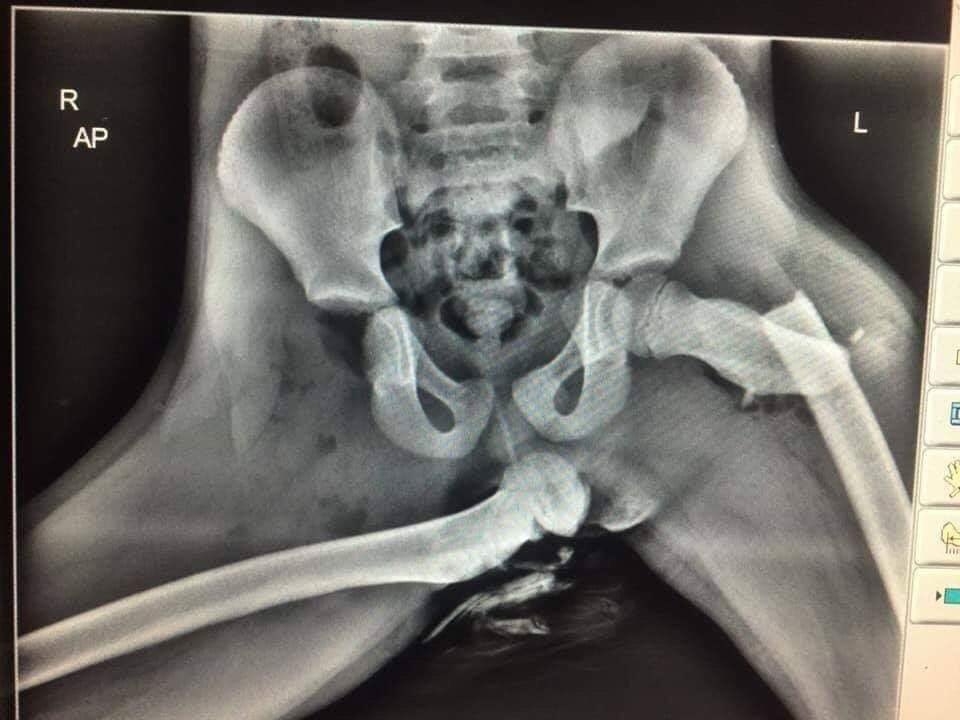

영국 웨일즈에서 근무하는 이안 프라이스 경사가 자신의 트위터에 해당 사고 피해자의 엑스레이 사진을 올렸다.

큰 사고를 입은 것처럼 뼈가 정상적인 위치에 있지 않는 모습으로 보인다.

사진을 올린 프라이스 경사는 트위터에 사진과 함께 “이는 충돌 당시 대시보드에 발을 올려둔 조수석 승객의 끔찍한 부상 사진”이라며 “만약 당신의 차량 탑승자가 이런 자세를 취하고 있다면 즉시 차를 세우고 이 사진을 보여달라”고 전했다.

그리고 결국 완전히 탈골된 오른쪽 대퇴골로 인해 영구 장애 판정을 받았다고 한다.